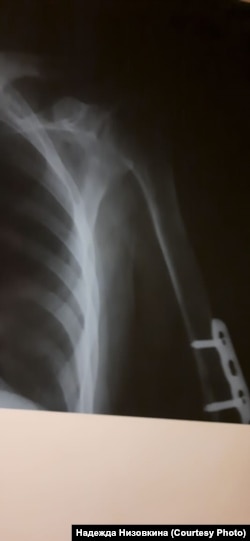

– Меня долгое время не пускали не то что в Советский отдел полиции, а даже во двор, все перекрыли! – возмущается адвокат Баирова Надежда Низовкина. – Подобное "задержание" и сокрытие человека – это, безусловно, преступление. Дмитрию же при этом еще и повредили руку – когда скрутили, задели штыри в руке, установленные после перелома, сейчас его мучают сильные боли. Потому что, найдя его через прокурора(!), мы добились, что его осмотрели медики, сделали снимки (медосвидетельствование показало повреждение мышечной ткани на месте сросшегося перелома), поставили обезболивающее, но продолжат ли его ставить – большой вопрос.

Рентген сломанной руки Дмитрия Баирова, Улан-Удэ, 28 января